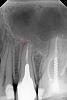

Kolchanov Опубликовано 9 сентября, 2013 Автор Поделиться Опубликовано 9 сентября, 2013 Вот в таком кривом зубе (14) я сейчас пытаюсь продать эндодонтию.http://i078.radikal.ru/1309/9f/625f845d15d5.jpgПломба стояла прямо на пульпе. Последняя возьми да и умри. В анамнезе боли, которые потом прошли, а в канале распад пульпы влажненький такой.Штифтик, что длиннее, в небном канале. А вот в щечном засада. Пока еще не ступень, но что-то очень уж криво. Обязательно ступень будет.http://s019.radikal.ru/i635/1309/4b/4425e1d260c8.jpgможет и третий канал где-то есть, но пока вот так. Очень сложный для меня зуб! Ссылка на комментарий

Kivilgar Опубликовано 9 сентября, 2013 Поделиться Опубликовано 9 сентября, 2013 А рядом кочергой 13? Я чет не пойму он куда смотрит в полости рта? Или он полностью ретинированный? Ссылка на комментарий

Kolchanov Опубликовано 9 сентября, 2013 Автор Поделиться Опубликовано 9 сентября, 2013 Да, это 13. Он указывает на северо-запад Его нет во рту. Сейчас подлечится и пойдет к ортодонту тянуть его. Ссылка на комментарий

M@estro Опубликовано 9 сентября, 2013 Поделиться Опубликовано 9 сентября, 2013 (изменено) Вот в таком кривом зубе (14) я сейчас пытаюсь продать эндодонтию. может и третий канал где-то есть, но пока вот так. Очень сложный для меня зуб! Подозреваю,что канала три. Вот,в пэйнте накидал : http://s1.ipicture.ru/uploads/20130909/UR5sRLnA.jpg Особенно ярко видно разделение щёчных. А на деле - микроскоп его знает. Уж больно изгиб резкий у щёчного. Изменено 9 сентября, 2013 пользователем M@estro Ссылка на комментарий

Kolchanov Опубликовано 9 сентября, 2013 Автор Поделиться Опубликовано 9 сентября, 2013 Попробую расшириться в четверг. Может чего найду. Тут хоть один щечный до конца бы дойти... Очень кривой зуб! Ссылка на комментарий